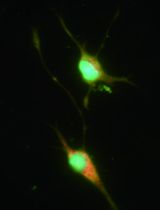

Olfactory ensheathing cells (OECs) are glial cells that express various antigens similar to astrocytes and Schwann cells such as glial fibrillary-associated protein (GFAP), S100-beta, p75 low-affinity nerve growth factor receptor, vimentin, nestin, and neuropeptide Y (Singh et al., 2013). Olfactory ensheathing cells release different neurotrophic factors and adhesion molecules that function in cellular growth and adhesions of central nervous system (Pastrana et al., 2007). In addition, these cells play an important role in the regeneration of the damaged central nervous system such as treatment of spinal cord injury and neurodegenerative diseases (Novikova et al., 2011). We select OECs as research material in our study as they have several advantage properties such as high migratory capacity, accessible source, differentiation from stem cells of nasal olfactory mucosa, and non-tumorigenicity behavior (Huang et al., 2008; Escada et al., 2009). This protocol describes a step-by-step procedure for the isolation of OECs from Human Olfactory Mucosa Specimen.